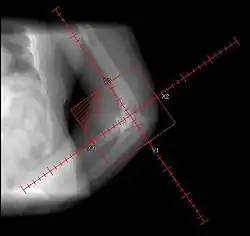

The only definitive diagnostic test in the early acute stage is a bone scan, which will show heterotopic ossification 7 – 10 days earlier than an x-ray. The three-phase bone scan may be the most sensitive method of detecting early heterotopic bone formation. However, an abnormality detected in the early phase may not progress to the formation of heterotopic bone. Another finding, often misinterpreted as early heterotopic bone formation, is an increased (early) uptake around the knees or the ankles in a patient with a very recent spinal cord injury. It is not clear exactly what this means, because these patients do not develop heterotopic bone formation. It has been hypothesized that this may be related to the autonomic nervous system and its control over circulation.[3]